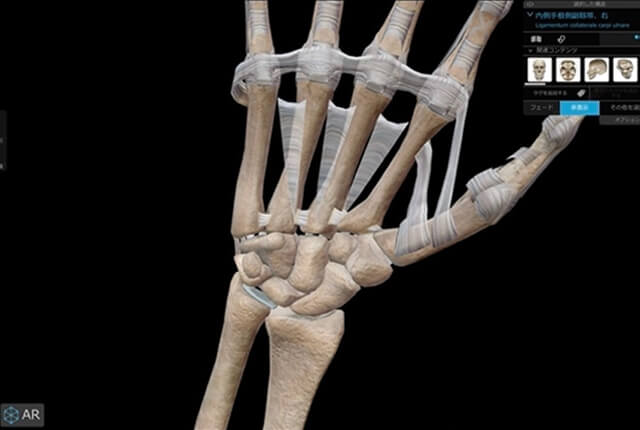

手関節の解剖

手関節は橈骨、尺骨、および8個の手根骨から成ります。

遠位橈尺関節(DRUJ)

橈骨と尺骨の遠位部の関節は遠位橈尺関節(DRUJ)と言います。

DRUJ、尺骨遠位、手根骨をつなぐ支持組織は三角線維軟骨複合体(TFCC)と言います。

三角線維軟骨複合体(TFCC)